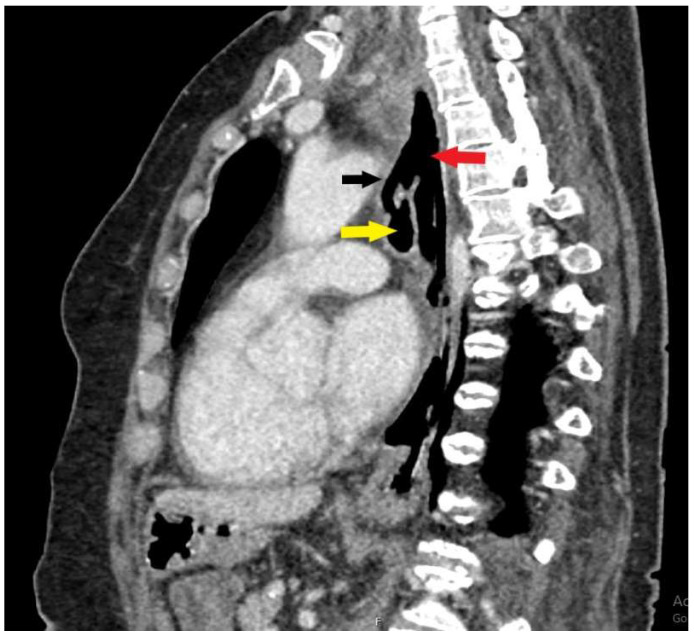

气消化瘘管是临床实践中的一个主要挑战。尽管最近内镜腔内修复技术有了很大的优势,但这个问题的发病率和死亡率都很高。特殊的问题是瘘管局部较高,累及食管和气管近端,这在成人中最常由插管后损伤引起。手术通常要求很高,而且是为那些其他侵入性较小的选择失败的患者保留的。在此,我们报告一例插管后气管食管瘘,经内镜血管塞置入成功治疗。

Aerodigestive fistulas represent a major challenge in clinical practice. This problem is burdened with severe morbidity and mortality, despite recent advantages in endoscopic endoluminal repair techniques. Special problems are fistulas localized higher, engaging the proximal esophagus and trachea, which in adults most often result from post-intubation injury. Surgery is generally demanding and reserved for the patients in whom other, less invasive options fail. Hereby, we present a case of post-intubation tracheoesophageal fistula, successfully treated with endoscopic vascular plug placement.